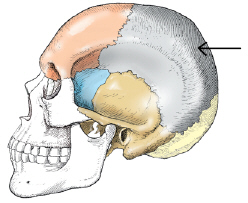

all of the following are cranial bones except the

maxillae

which of the following skull types is considered average in size and shape

mesocephalic

which plane of the head is placed parallel to the plane of the image receptor for a lateral projection of the skull

midsagittal

Which projection of the skull requires MSP be positioned parallel and interpupillary line perpendicular to IR plane

Lateral